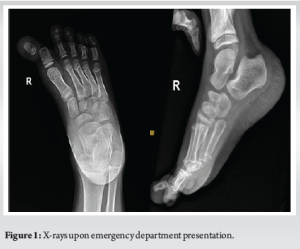

The patient was initially attended and examined by an emergency physician who then started intravenous (IV) cefazolin and consulted orthopedic surgery as a case of open first interphalangeal joint dislocation. Upon examination from the orthopedic resident oncall, the patient was found to have an approximately 3 cm transverse laceration along the plantar and lateral aspect of the base of the right big toe. After irrigation with normal saline, no visible contamination was noted, and the articular surface of the proximal phalanx was exposed. Cap refill noted to be <2 s and gross toe sensation was intact. Radiographs confirmed a medial HIJ dislocation. The nature of condition and management plan was discussed with the patient and his parents, and consents were obtained. After obtaining narcotic analgesia, closed reduction was successfully done by the orthopedic resident oncall, utilizing a traction and lateral translation maneuver, the wound was covered by wet-to-dry sterile gauze and immobilized with plaster and buddy taping. The patient was then booked for exploration, irrigation, and debridement with K-wire fixation as CAT-II. The patient underwent surgical intervention under general anesthesia the next day, found to have an intact FHL tendon and volar plate, the capsule was repaired, wound was irrigated thoroughly, and the HIP joint was fixed with a retrograde 1.8 mm Kirschner wire, wound closed primarily with prolene. Proper K-wire placement and joint reduction confirmed under orthogonal intra-operative radiographs utilizing C-arm. Cap refill was noted to be <2 s. The joint was immobilized with a short backslab with extension to toes, reflected distally to cover the bent K-wire tip to avoid inadvertent removal by the child (Fig. 3).

The patient was discharged after 48 h of IV antibiotics (cefazolin) post-operatively, advised forefoot off-loading and prescribed oral cefuroxime for 7 days with a follow-up in the clinic the following week for wound check. Two weeks post-surgery, the wound was healed, and sutures were removed, big toe sensation was preserved, X-rays showed a stable implant and HIP joint. At 4 weeks post-operatively, the K-wire was removed, and radiographs showed a stable HIP joint. At 12 weeks, the patient had a painlessly mobile great toe. At 24 weeks follow-up the patient was found to have a painless full right big toe range of motion and was hence discharged from the clinic (Fig. 4 and 5).